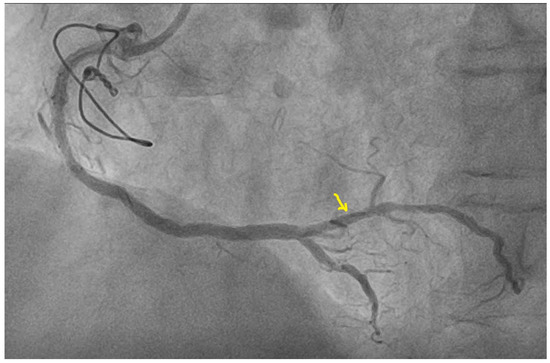

The echocardiographic measurements are normal, with a normal global systolic function and a left ventricular ejection fraction (LVEF) of 50%, but the LV wall motion is weak on the side (Figure 2).

We used speckle-tracking echography in 4-3- and 2-chamber apical incidences to calculate the global LV strain, which was found to be significantly decreased (<12%, normal range > 20%). We then assessed the myocardial work (MW) of the patient. The LV-pressure strain loop (PSL) in this new method is derived from non-invasively acquired brachial artery cuff pressure and generated by adjusting the profile of a reference LV pressure curve according to the duration of the isovolumic and ejection phases, as defined by the echocardiography timing of aortic and mitral valve events. After calculating the global LV strain, measurements of brachial blood pressure and time of valvular events were utilized to obtain the LV-PSL with currently available echocardiographic software. The area of the PSL represents approximately the MW and is computed by multiplying the rate of segmental shortening, obtained by integrating the strain curve, by the momentary LV pressure. This product is a measure of instantaneous power, which is incorporated throughout the cardiac cycle to generate MW, which is given in mmHg%. In addition to the MW index (work assessed from mitral valve closure to mitral valve opening), segments were examined for wasted work (WW) and constructive work (CW), with global values calculated as the mean of all segmental values. The global myocardial work index (1123 mmHg%; normal value > 1200 mmHg%), which measures LV work during systole, was reduced. As shown in Figure 3, myocardial work efficiency, which is calculated as the ratio of constructive to wasted work, was also found to be lower (85%, normal value > 90%).

The Bull’s-eye polar map representation of the global longitudinal strain of the LV, with 17 wall segments divided from apex to base and the visualization of a circumscribed blue area in specific segments, allows one to determine the distribution of blood flow abnormalities based on the culprit coronary artery.

On the polar map of the GLS, the regions with the lowest longitudinal strains were the anterior, lateral, and posterior ones, with the smallest value being observed at the level of the anterior region (−4%), as shown in Figure 3A.

The polar map of the global MW index (Figure 3B) also showed that the anterior, lateral, and posterior regions of the LV wall present lower values of the MW index, the lowest value being observed at the level of the posterior area (447 mmHg%).

Figure 2. Two-dimensional echocardiography and Bull’s-eye map representation of global longitudinal strain of the left ventricle.